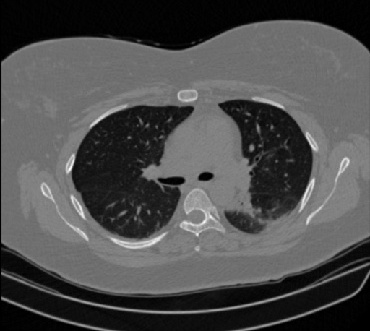

It should be mentioned that for explainability purposes [7, 8, 9], an anchor set was generated for the COV19-CT-DB database [5]. This included 11 anchors, each representing a respective 3-D CT scan obtained through an appropriate clustering procedure. Figure 2 shows a series of slices from a COVID-19 case, whereas Figure 3 shows a series of slices from a non COVID-19 case.